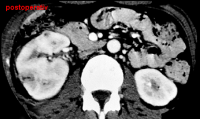

Die Nierenfreilegung und Abszessdrainage bzw. der postoperative Krankheitsverlauf im obigen Fall (s. Abbildung 6) sind in den Abbildungen dargestellt (Abbildung 9,10).

In einer weiteren Beobachtung bei einem 19jährigen Jugendlichen konnte der linksseitige Nierenabszess durch alleinige antibiotische Behandlung beherrscht werden (Abbildung 11).